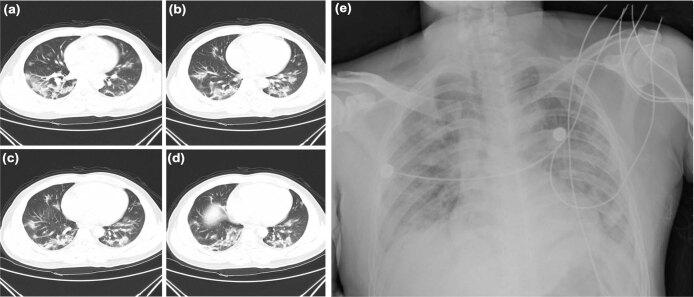

Emerging infectious diseases, such as severe acute respiratory syndrome (SARS) and Zika virus disease, present a major threat to public health. Despite intense research efforts, how, when and where new diseases appear are still a source of considerable uncertainty. A severe respiratory disease was recently reported in Wuhan, Hubei province, China. As of 25 January 2020, at least 1,975 cases had been reported since the first patient was hospitalized on 12 December 2019. Epidemiological investigations have suggested that the outbreak was associated with a seafood market in Wuhan. Here we study a single patient who was a worker at the market and who was admitted to the Central Hospital of Wuhan on 26 December 2019 while experiencing a severe respiratory syndrome that included fever, dizziness and a cough. Metagenomic RNA sequencing of a sample of bronchoalveolar lavage fluid from the patient identified a new RNA virus strain from the family Coronaviridae, which is designated here 'WH-Human 1' coronavirus (and has also been referred to as '2019-nCoV'). Phylogenetic analysis of the complete viral genome (29,903 nucleotides) revealed that the virus was most closely related (89.1% nucleotide similarity) to a group of SARS-like coronaviruses (genus Betacoronavirus, subgenus Sarbecovirus) that had previously been found in bats in China. This outbreak highlights the ongoing ability of viral spill-over from animals to cause severe disease in humans.

新发传染病,如严重急性呼吸综合征(SARS)和寨卡病毒病,对公共卫生构成重大威胁。尽管研究力度很大,但新疾病的出现时间、地点和方式仍然存在相当大的不确定性。最近在中国湖北省武汉市报告了一种严重的呼吸道疾病。截至 2020 年 1 月 25 日,自 2019 年 12 月 12 日首例患者住院以来,已报告至少 1975 例病例。流行病学调查表明,此次疫情与武汉市一家海鲜市场有关。在此,我们研究了一名患者,他是该市场的一名工人,于 2019 年 12 月 26 日因严重呼吸综合征住院,该综合征包括发热、头晕和咳嗽。对该患者支气管肺泡灌洗液样本进行的宏基因组 RNA 测序鉴定出一种新型冠状病毒科 RNA 病毒株,我们将其命名为“WH-Human 1”冠状病毒(也称为“2019-nCoV”)。对完整病毒基因组(29903 个核苷酸)的系统发育分析表明,该病毒与一组在中国蝙蝠中发现的 SARS 样冠状病毒(冠状病毒科,贝塔冠状病毒亚科)最为密切相关(核苷酸相似度 89.1%)。此次疫情突显了病毒从动物溢出并导致人类严重疾病的持续能力。